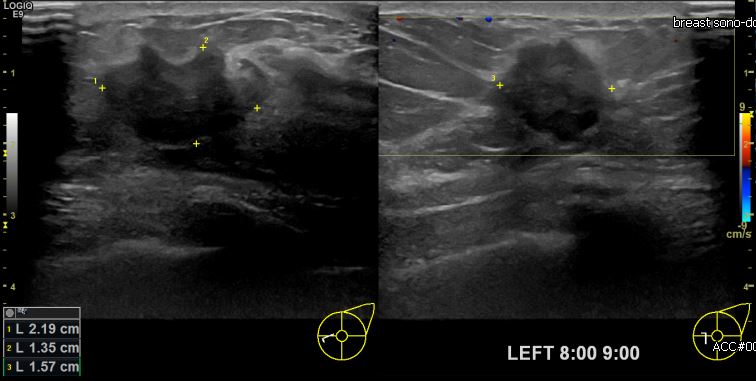

상기환자 건강검진상 이상소견으로 내원하신 50대 여성분으로 본원 초음파상 좌측 8시에서 9시 방향에 의심스러운 멍울 조직검사 시행하여 좌측 침윤성 유관암 진단되었습니다.